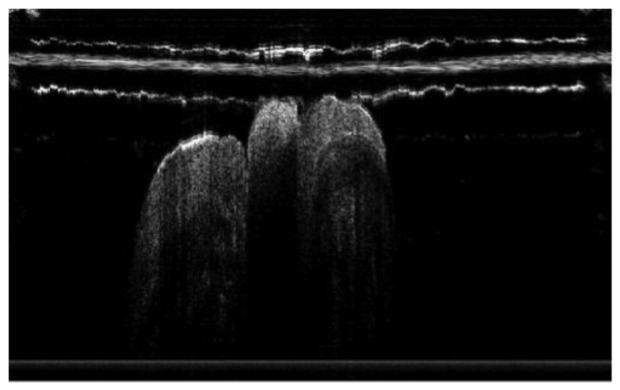

Figure 7.

In vivo OCT image of microleakage detected by a custom-made dental optical probe (reprinted from reference [55]).